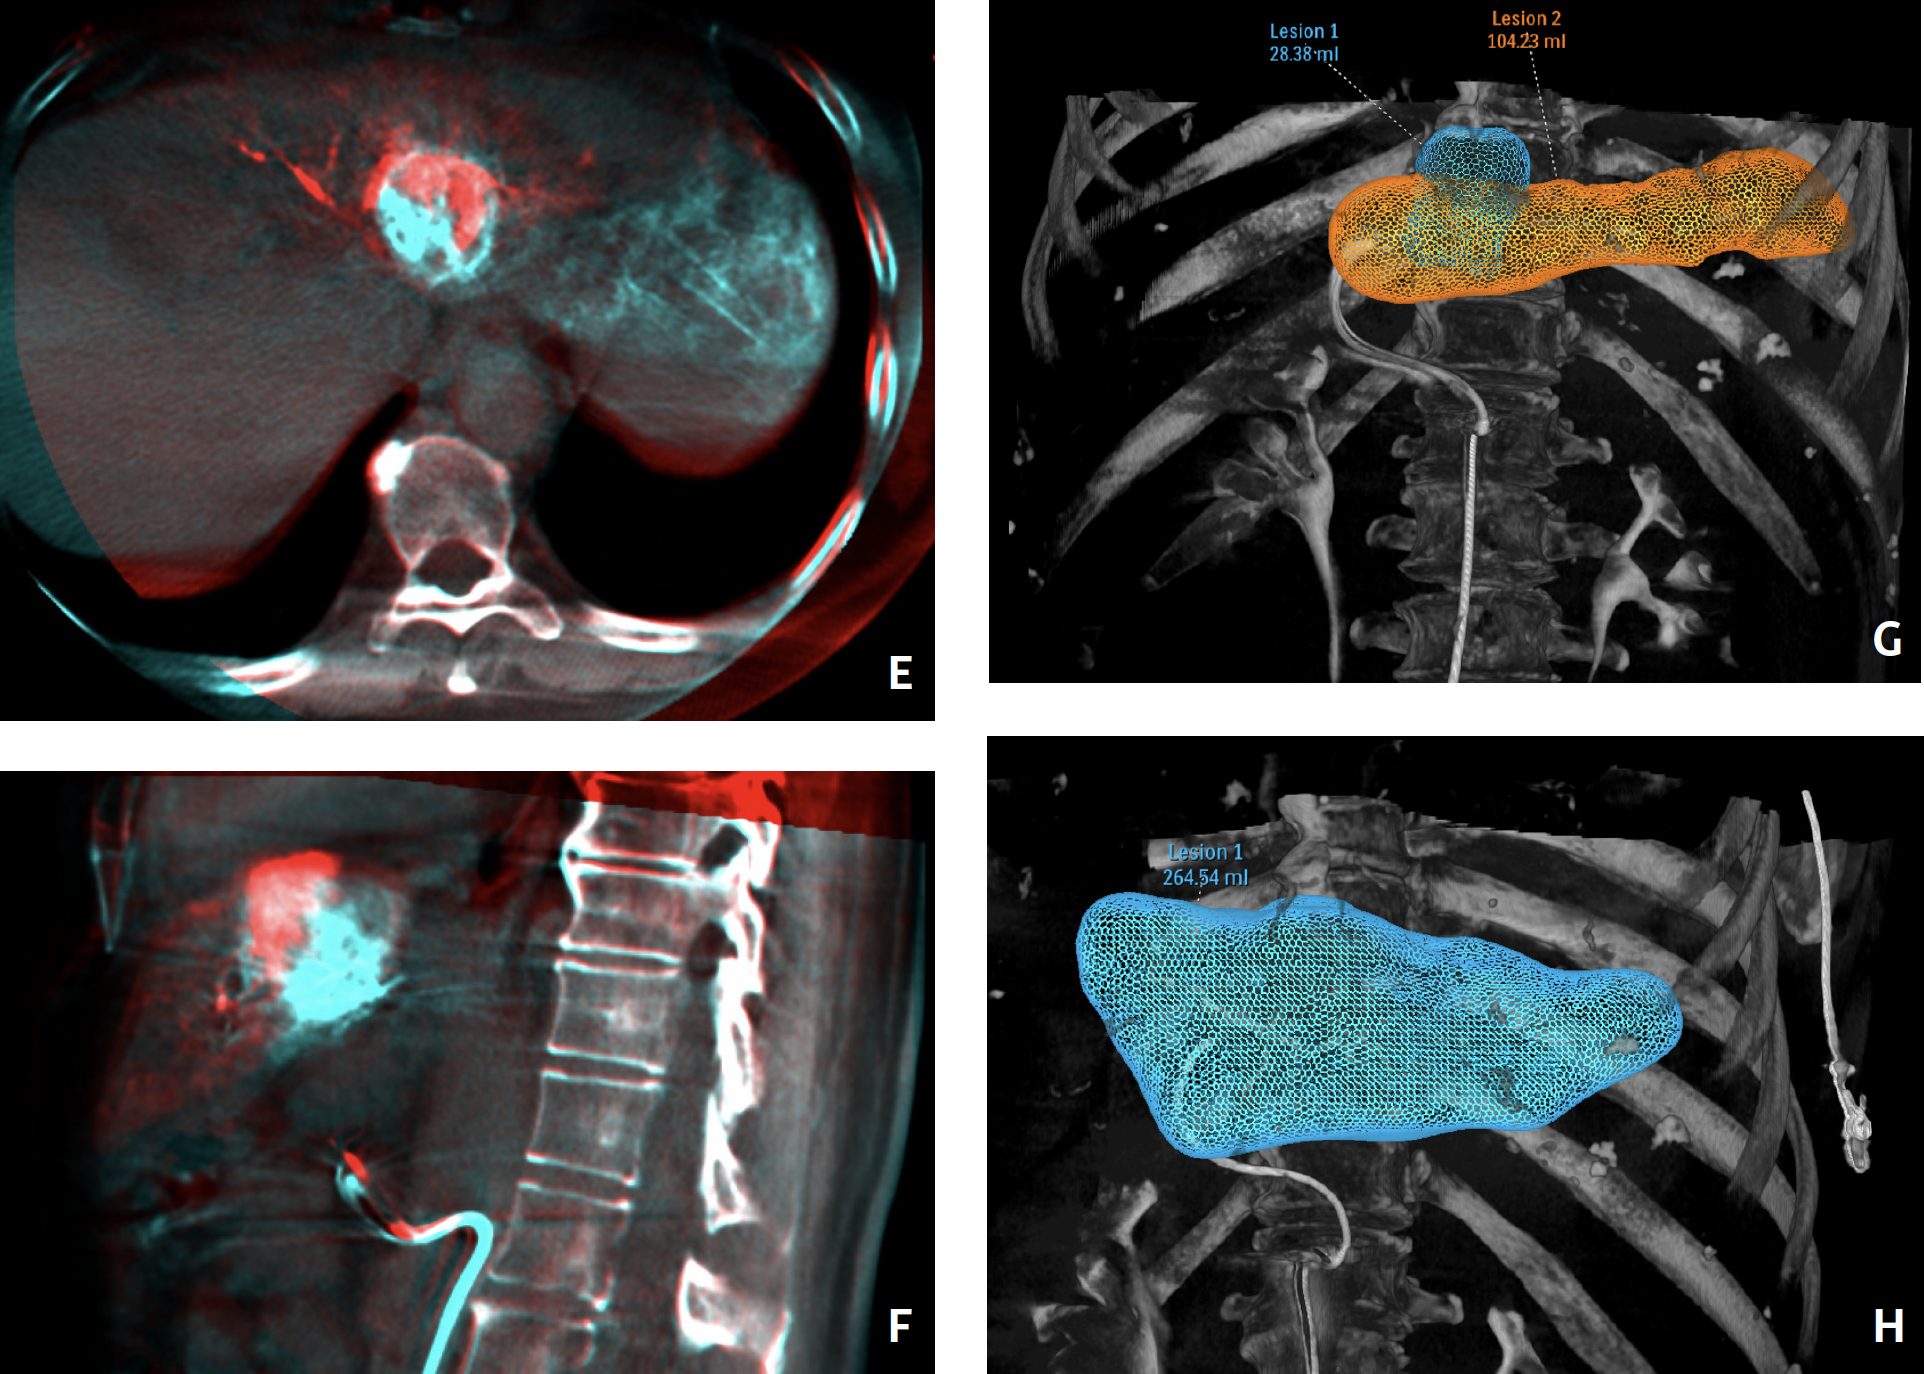

As an example, I recently had a patient who was undergoing treatment for hepatocellular carcinoma. I used the cone-beam CT feature to scan the liver with the Angio machine and I found that the artery I thought was supplying the tumor supplied only part of the tumor, while another artery supplied the other half of the tumor. Without this specialized software, I would have done the procedure on only the first artery, brought the patient to follow-up, and discovered that only half the tumor was treated, necessitating another treatment session. Because I had the cone-beam CT, EmboGuide software, and Fusion software (Philips), I was able to fuse multiple cone-beam CT images together to show that the entire tumor would be covered by injecting into 2 arteries. Philips software enabled me to optimize this patient’s treatment in only 1 session. Each tumor is different, and the software allows us to provide a personalized approach to each patient.

Our suite also features Zenition mobile C-arms and EPIQ ultrasound machines (Philips). Each modality has its own function, increasing the efficiency of our workflow. The ultrasound system features Fusion Navigation software, which allows us to biopsy and ablate lesions that are in difficult locations, such as those abutting critical structures, by allowing precise needle placement inside the tumor that we want to biopsy or ablate in the liver and other organs. This ability has resulted in an increase in the number of patients who are viable candidates for image-guided cancer treatments, because we are now able to do procedures that were once impossible. The Fusion Navigation software provides greater accuracy and minimizes complications arising from a tumor in close proximity to vital or important structures. The software has increased the scope of our practice while reducing our complication rates.